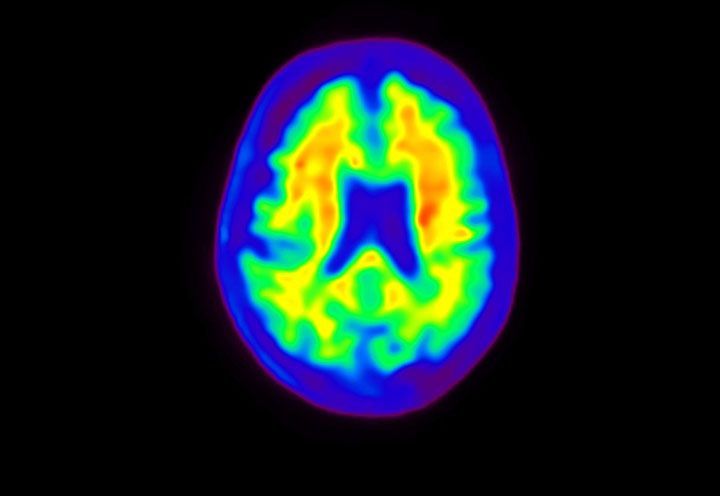

Head / Case4 : Amyloid

Axial

Courtesy : Kindai University Hospital

- Imaging protocol

- Injected dose: 3.21 MBq/kg, 18F-Flutemetamol

- Uptake time: 100 minutes

- Scan time: 20 minutes